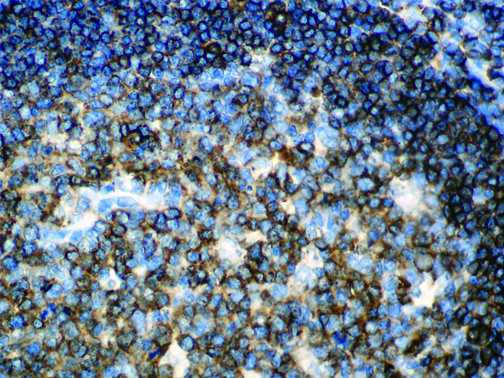

It is the ICU physician who is most likely to witness one of the deadliest manifestations of the abnormal immunological response, the cytokine storm syndrome (CSS). This response is also referred to by some as the cytokine release syndrome (CRS). CSS is characterized by continuous activation and expansion of macrophage and lymphocyte populations, which secrete large amounts of cytokines, causing the cytokine storm. This massive cytokine release is akin to hemophagocytic lymphohistiocytosis (HLH) disease, a syndrome characterized by initial unchecked and persistent activation of cytotoxic T lymphocytes and NK cells.

Clinical and laboratory manifestations of HLH include fever, enlarged liver and/or spleen, neurologic dysfunction, coagulopathy, liver dysfunction, cytopenias (i.e., low levels of erythrocytes, leukocytes, and/or platelets), hypertriglyceridemia, hyperferritinemia, hemophagocytosis, and eventually diminished NK cell activity as the immune system becomes progressively paralyzed. HLH can be familial (primary HLH) or secondary to another disease process (sHLH), such as rheumatic disease, in which it is referred to as macrophage activation syndrome (MAS, characterized by elevated ferritin).